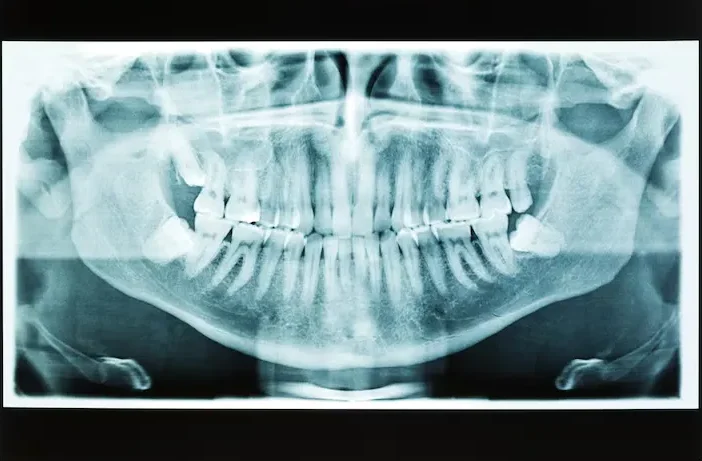

Panoromic X-rays

This is one large x-ray that captures an image of your entire mouth, jaw and sinus area. It is mainly used as a diagnostic tool when patients are experiencing dental issues